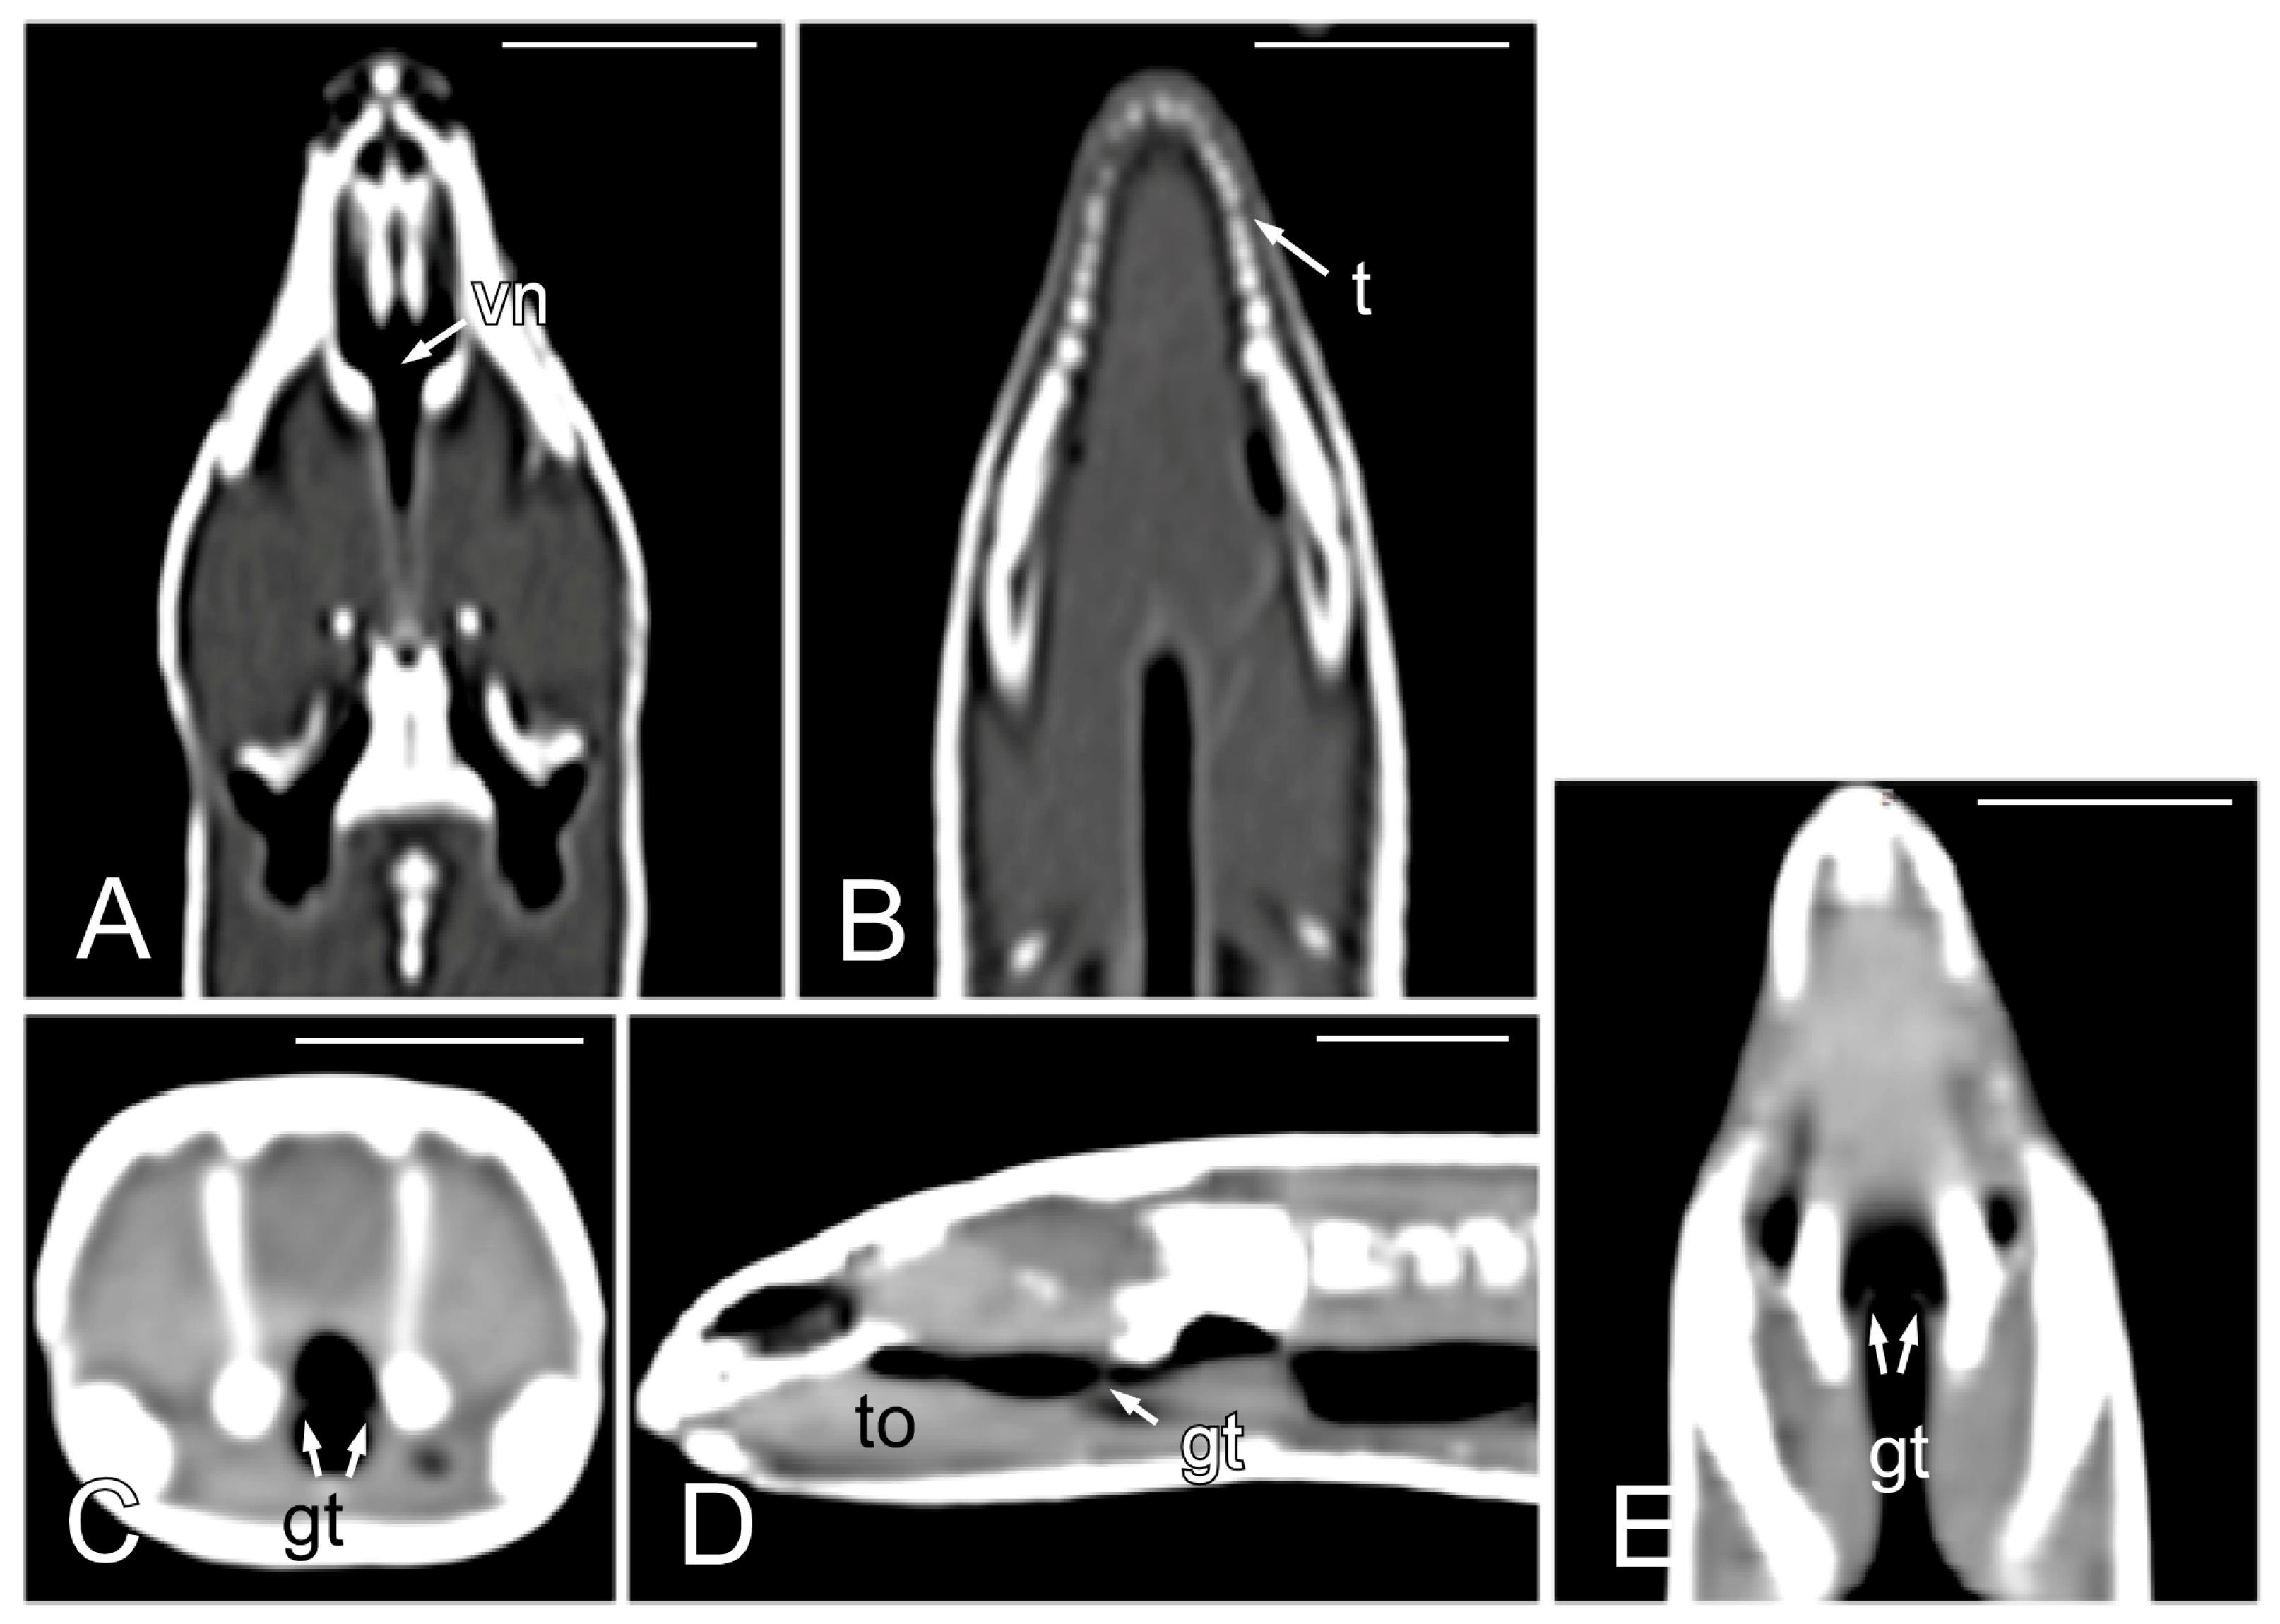

The opening of the vomeronasal organ together with the choanae was identified in the dorsal plane as a V-shaped structure delimited by thin hyperattenuating margins (Figure 4A). The teeth were more distinctly evaluated in the dorsal plane (Figure 4B). The tongue appeared as a hypoattenuating structure located in the ventral part of oral cavity and was more clearly visible in the sagittal plane (Figure 4D). The glottis (Figure 4C–E) was identified as a thin, soft tissue structure with a central opening between the oral and pharyngeal cavities. Although it was visible in the transverse, sagittal, and dorsal planes, it was easier to identify in the latter two.

Figure 4.

The CT images of Pseudopus apodus in the dorsal (A,B,E), transverse (C) and sagittal (D) planes showing the opening of the vomeronasal organ and the choanae (A), teeth (B), tongue (D) and glottis (C–E). See the list for abbreviations. Bar = 10 mm.

In the oral cavity, a wide overture that coincides with the vomeronasal organ and the choanae opening stands out (Figure 3A,B). The presence of the glottis, quite cranial in the oral cavity, and visible when the mouth is opened (Figure 3C), is noteworthy. The upper airways also include a larynx and pharynx that do not show special details. To complete the macroscopic description of the oral cavity, the cone-shaped, slightly asymmetrical teeth and the forked tongue should also be highlighted (Figure 3C).

Figure 3.

The images of the oral cavity of Pseudopus apodus showing the opening of the vomeronasal organ and the choanae (A,B), the tongue (C), and the glottis (C). See the list for abbreviations. Bar = 1 mm.